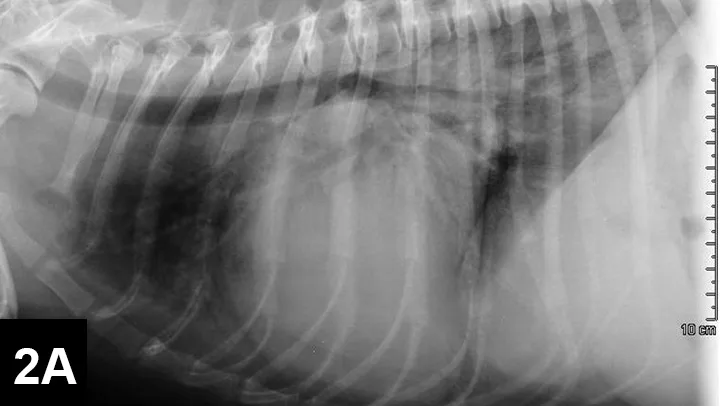

FIGURE 2A

Right lateral thoracic radiograph

A sinus rhythm (HR is ~150 bpm) and left ventricular enlargement pattern were noted on ECG: the sensitivity was decreased to 5 mm/mV, and R waves measured ~3 mV (upper end of normal R-wave height is 2.5 mV). Thoracic radiographs revealed severe left atrial enlargement with moderate left ventricular enlargement. There was a moderate interstitial to alveolar pulmonary pattern most pronounced in the caudodorsal lung fields, which is consistent with left-sided congestive heart failure resulting from degenerative mitral valve disease.